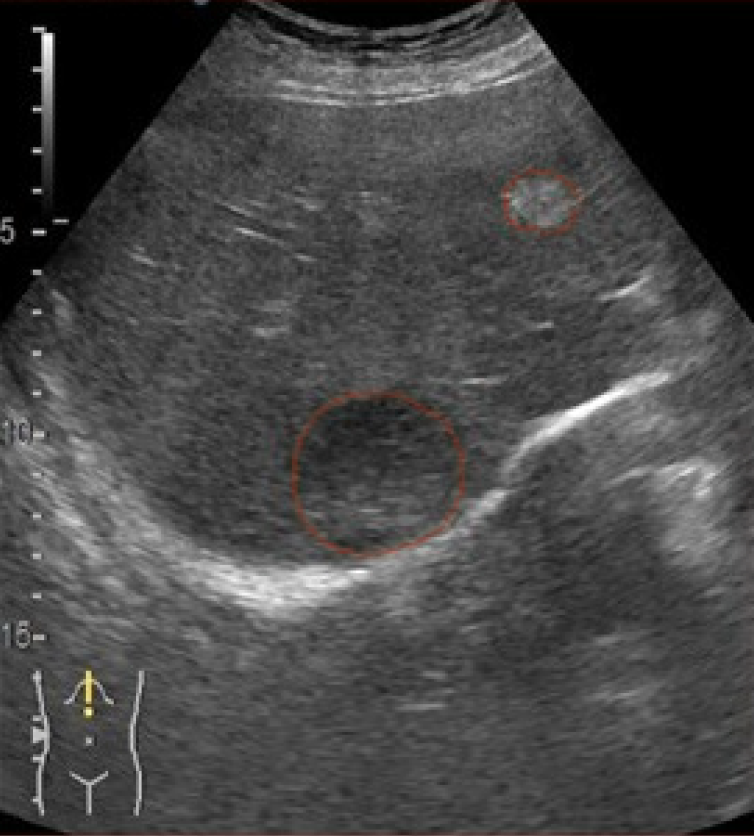

Figure 4 Example of automated lesion segmentation vs expert ground truth.

A: Original B-mode contrast-enhanced ultrasound image with a visible liver lesion; B: Gastroenterologist’s manual segmentation mask (ground truth); C: U-Net model predicted lesion mask on the same frame.